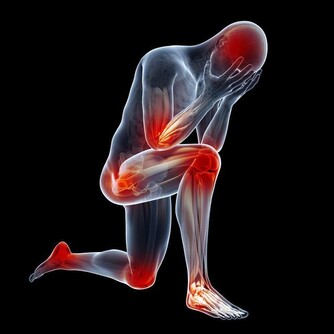

長期高血糖會對身體的許多器官造成傷害,但積極改變生活方式有助於降低血糖和預防糖尿病並發症。採取行動永遠不會太晚,即使你已經患有糖尿病很多年,仍然可以做出改變以改善健康狀況。

保持血糖達到預期目標,可以幫你防止大型和小型血管受損。但你需要確保自己清楚地了解血糖目標是什麼,過高和過低的血糖都是危險的。